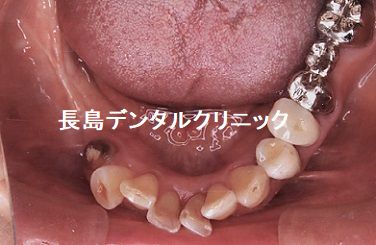

1、インプラント埋入前

数年前に他院で右下(黄色い矢印)にインプラントを入れましたが、

感染し骨が大きく吸収してしまい再度インプラントを希望されました

が、骨が少ないということでインプラント治療を断られた患者様が、

当クリニックの患者様のご紹介で来院されました。赤い矢印が歯があ

った時の歯茎の位置ですが、それと比べて黄色い矢印の部分は大きく

骨が吸収してしています。下顎の奥歯では神経までの骨の厚みが重要